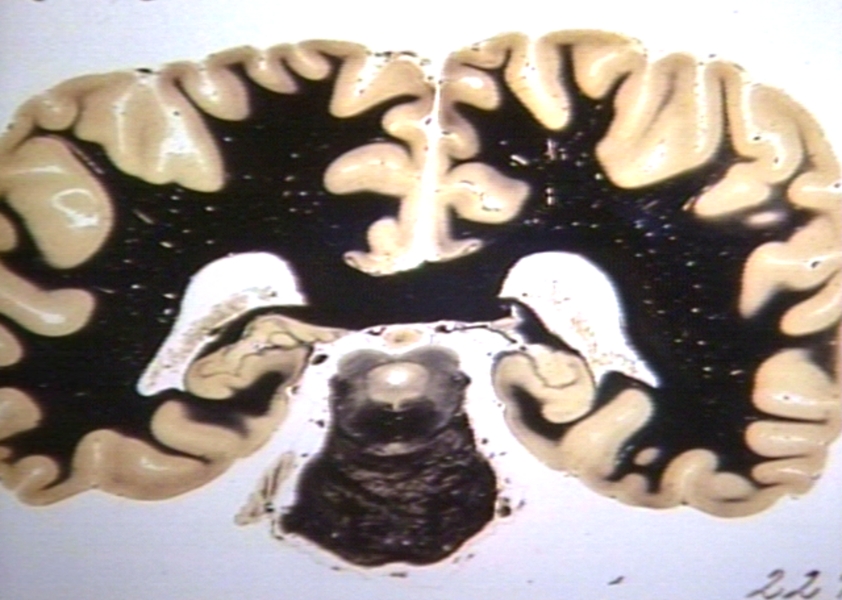

HISTOLOGY: NERVOUS: BRAIN: OCCIPITAL CORTEX, SPLENIUM AND MIDBRAIN, AFIP SERIES; AT THE LEVEL OF THE OCCIPITAL HORN AND MIDBRAIN